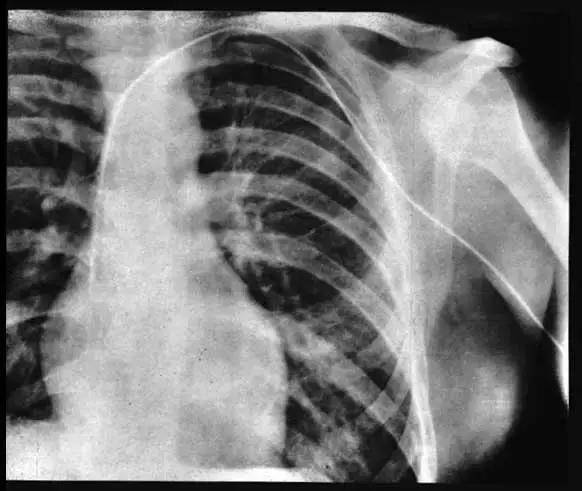

隨後,她便攙扶著福斯曼走到了樓下的X射線室。

通過鏡子裡螢光屏的指引,福斯曼再一步一步地將導管深入自己的身體裡。

福斯曼捏著導管,緊緊盯著鏡子裡的景象。

導管越來越深,X射線室裡的每個人都屏住了呼吸,生怕一個不小心,面前這位瘋狂醫生就會死去。

終於,當導管深入福斯曼體內65釐米時,導管進入了福斯曼的右心房。

那一刻,看著X射線螢光屏上的圖像,所有人都不由自主感嘆。

福斯曼自己也覺得十不可思議,當導管進入脆弱而敏感的心臟,他不僅沒有感受到絲毫的疼痛,反而「感受到了一絲如太陽般的暖意」。

福斯曼心臟導管術X射線片

此外,他還將50%的碘化鈉溶液(最初的造影劑,不透X射線)注入導管,拍攝了極淡的右心影像片。